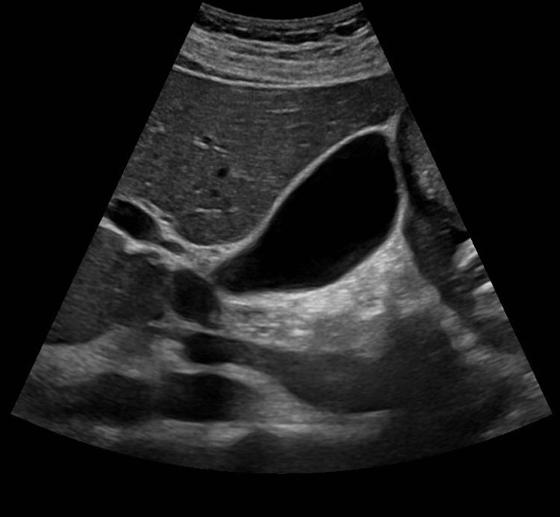

Gallbladder ultrasound is a quick, accurate, and non-invasive test that plays a crucial role in diagnosing many gallbladder conditions.

This common scan is the preferred choice because it delivers precise imaging without exposing patients to radiation. With over 35 years of experience, I am highly skilled in detecting conditions such as gallstones, gallbladder polyps, inflammation (cholecystitis), stones or obstructions in the bile duct, gallbladder tumours, mucocoeles, and complications like abscesses or perforation. Using my expertise at The Health Suite, most scans are available at short notice, and results are usually available on the same day.

A gallbladder ultrasound test is the trusted first-choice imaging method for diagnosing a wide range of gallbladder issues, from mild inflammation to more serious conditions.

This ultrasound can identify gallstones, polyps, cholecystitis, bile duct obstruction, tumours, mucocoele, abscesses, and perforation.

It provides accurate, real-time images for reliable diagnosis of gallbladder diseases, helping guide quick and appropriate treatment decisions.